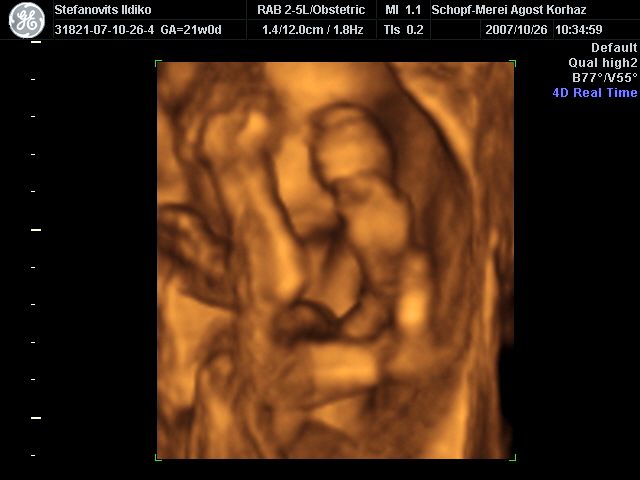

4D Ultrahang - 21+1 (07/10/26, Bp.)

4D - 6